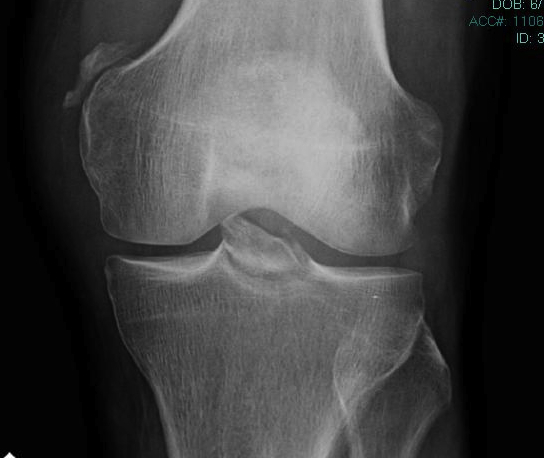

Bony Avulsion

Chronic bony avulsion PCL

Posterior subluxation of tibia

Grade 3 PCL disruption - posterior tibia subluxed behind posterior aspect femoral condyles